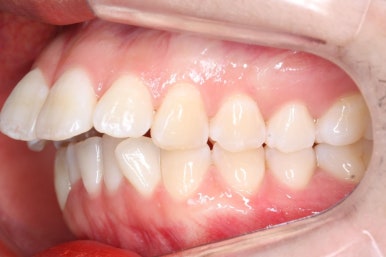

다시 이번 환자분으로 돌아가, 입 안모습을 보시겠습니다.

부산무턱교정 키다리아저씨치과에서 처음 내원하셨을 당시의 입 안의 모습입니다.

아래턱이 작아서 상대적으로 윗니들이 많이 돌출되었고, 뻐드러져 있습니다. 윗니들이 배열되어 있는 형태도 V자에 가깝게 입천장이 좁은 양상입니다.